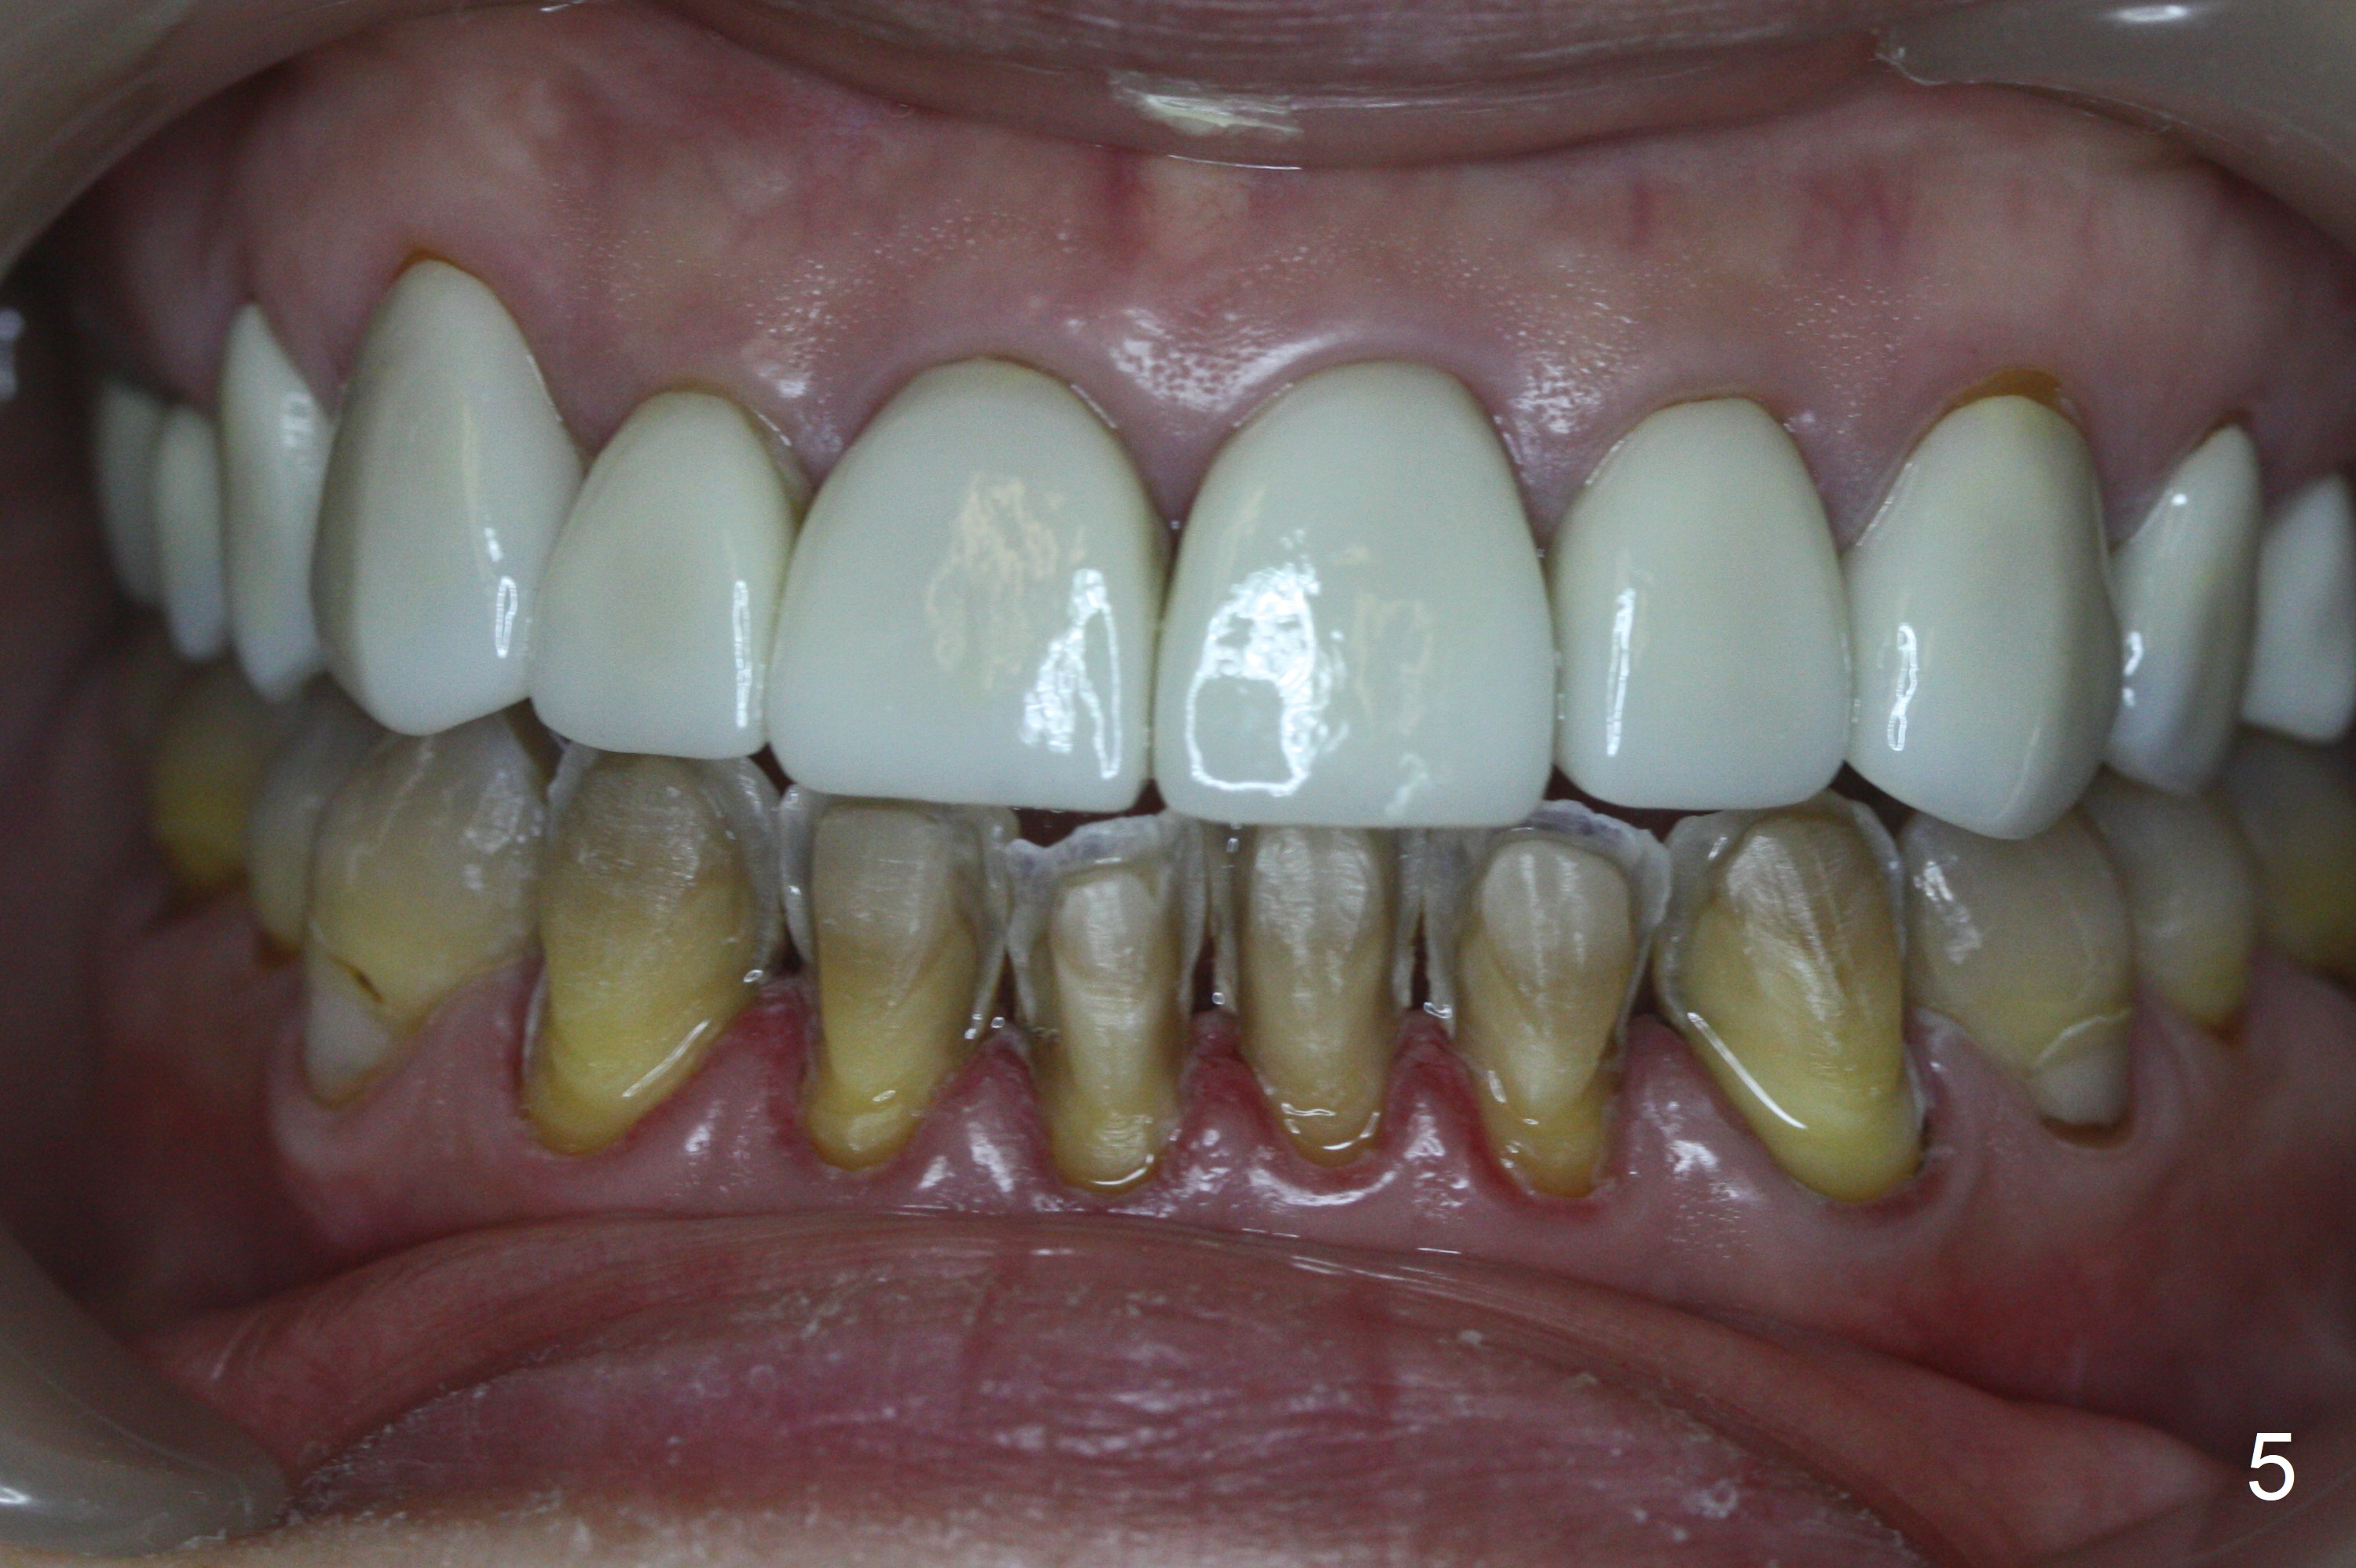

A 46-year-old woman has Tetracycline teeth. She is pleased with upper veneers and wants to do the same for the lower anterior teeth, which are crowding (Fig.1,2). Wax up (Fig.3,4) lays foundation for fabrication of reduction and provisional stents.

After prep (Fig.5), stump shade is chosen (Fig.6). Although B1 was selected for the upper veneers (Fig.7), the patient prefers to have A1 for the lower ones (Fig.8).